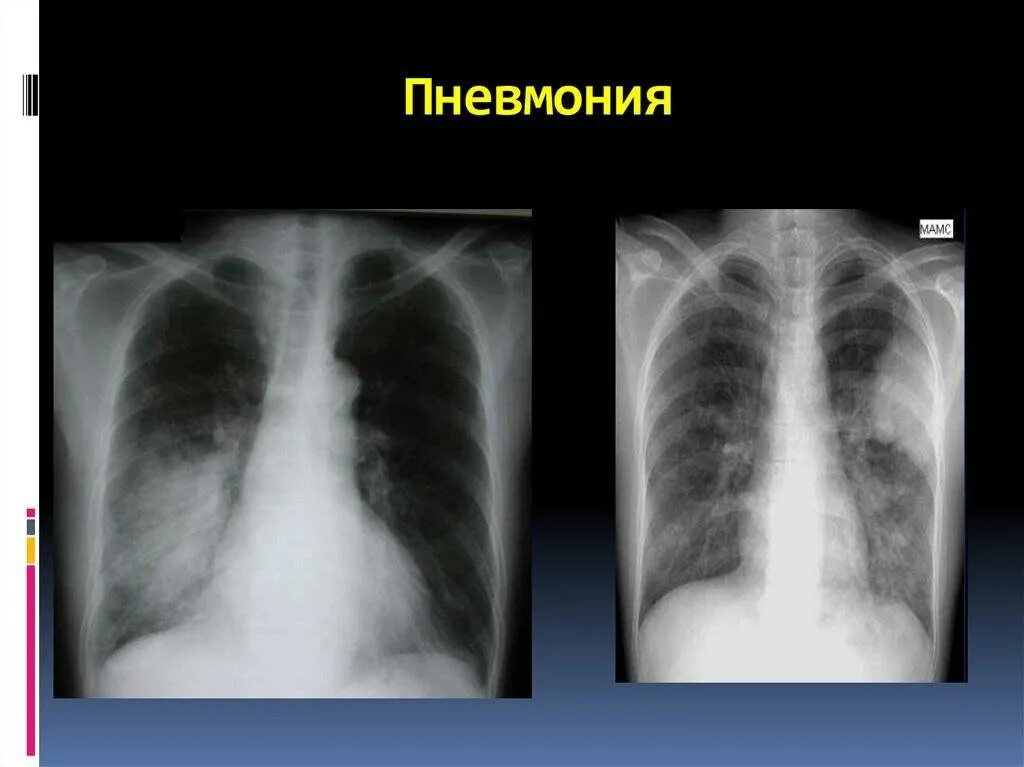

Как отличить воспаление легких